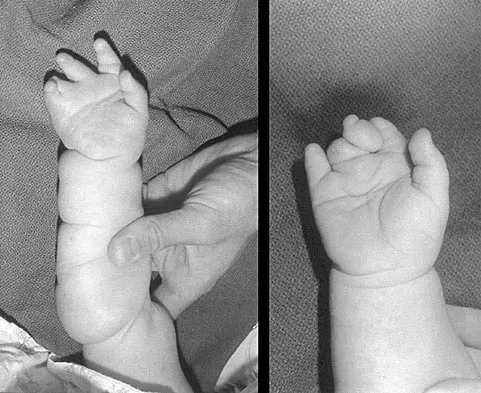

Question 68

A 1-year-old infant has the hand deformities shown in Figure 40. What pathologic process is the most likely cause of these deformities?

Explanation